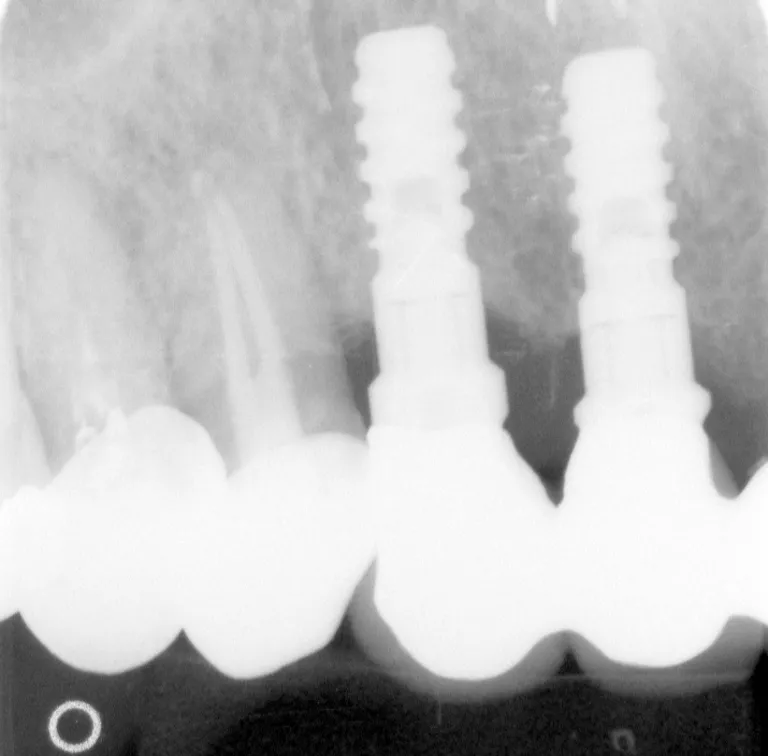

インプラント

取り外し式の入れ歯では満足できない場合に金属を埋め込み その上に歯を作るインプラント治療が行われています  取り外し式の入れ歯では満足できない場合、現在は顎の骨に直接チタン製の金属を埋め込んで、その上に歯を作るインプラント治療が行われています。

詳しくは、オプション治療をご覧下さい。

※画像をクリックで拡大されます

インプラント治療の詳細